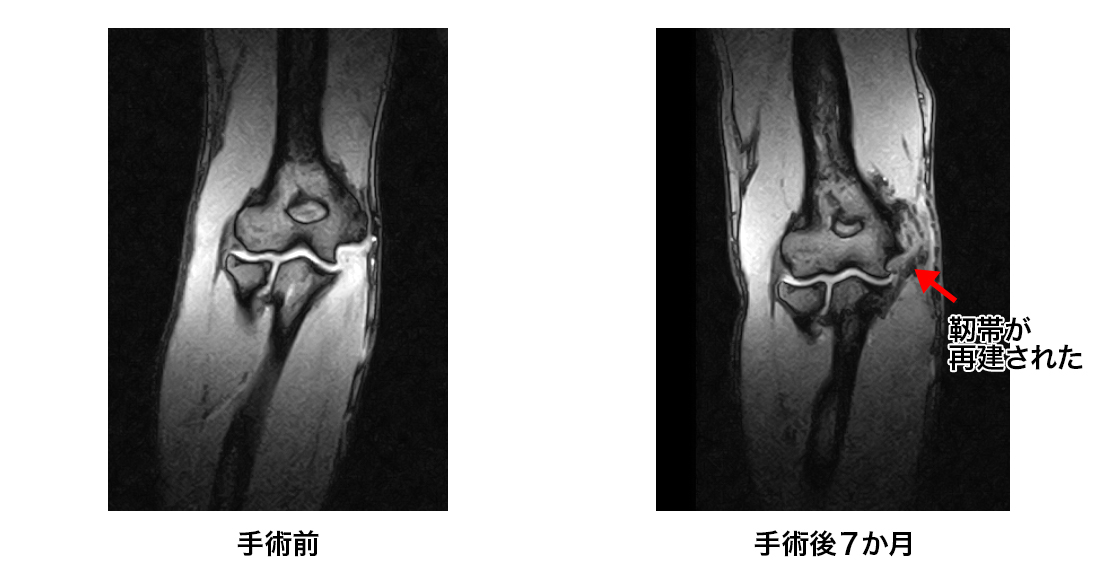

・内側側副靭帯再建術(いわゆるトミージョン)

野球肘2

症例1

17歳ハンドボール選手

手術後7ヶ月でハンドボールに完全復帰した。